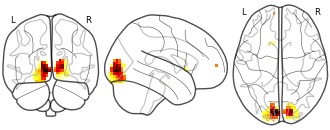

Data from: Mapping Lesions That Cause Psychosis to a Human Brain Circuit and...

EmailClick to copy linkLink copied Cite(2025). Mapping Lesions That Cause Psychosis to a Human Brain Circuit and Proposed Stimulation Target [Dataset]. http://identifiers.org/neurovault.collection:20510zipAvailable download formatsUnique identifierhttps://identifiers.org/neurovault.collection:20510Dataset updatedApr 29, 2025License

Cite(2025). Mapping Lesions That Cause Psychosis to a Human Brain Circuit and Proposed Stimulation Target [Dataset]. http://identifiers.org/neurovault.collection:20510zipAvailable download formatsUnique identifierhttps://identifiers.org/neurovault.collection:20510Dataset updatedApr 29, 2025LicenseCC0 1.0 Universal Public Domain Dedicationhttps://creativecommons.org/publicdomain/zero/1.0/

License information was derived automaticallyDescriptionA collection of 1 brain maps. Each brain map is a 3D array of values representing properties of the brain at different locations.

Collection description

Pines AR, Frandsen SB, Drew W, Meyer GM, Howard C, Palm ST, Schaper FLWVJ, Lin C, Butenko K, Ferguson MA, Friedrich MU, Grafman JH, Kappel AD, Neudorfer C, Rost NS, Sanderson LL, Taylor JJ, Wu O, Kletenik I, Vogel JW, Cohen AL, Horn A, Fox MD, Silbersweig D, Siddiqi SH. Mapping Lesions That Cause Psychosis to a Human Brain Circuit and Proposed Stimulation Target. JAMA Psychiatry. 2025 Apr 1;82(4):368-378.